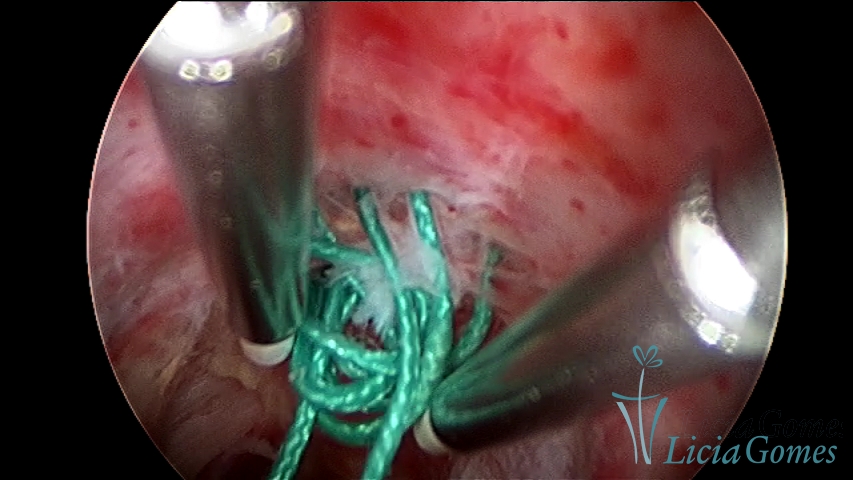

Retraction of a cesarean section scar with a non-absorbable suture for 30 years; resection with bipolar energy.